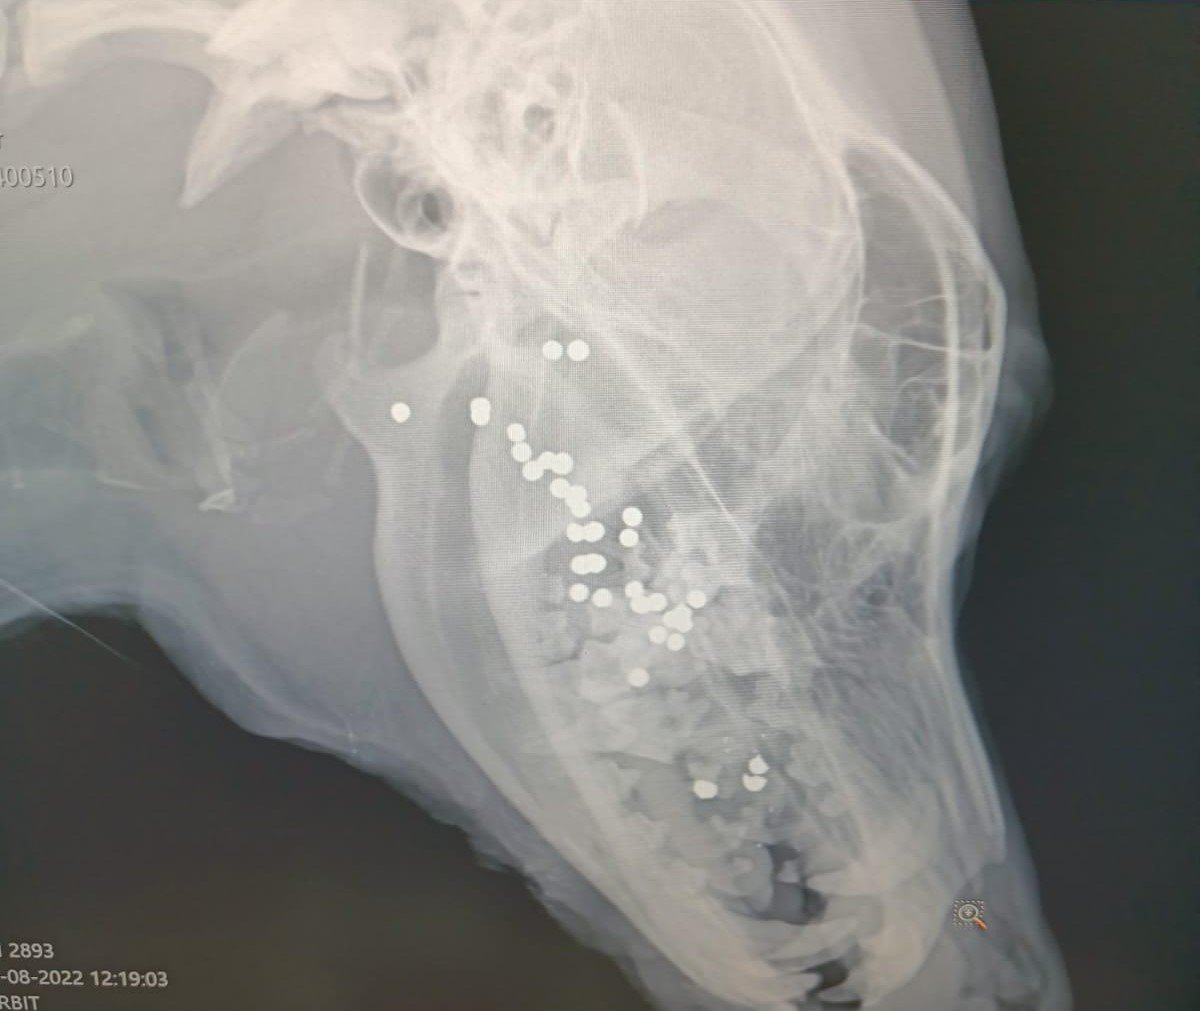

Yalım, yaralı köpeği veterinere götürdü. Köpeğin dilinin koptuğu, ağzının içerisinde müdahale edilemeyecek durumda saçmaların bulunduğu tespit edildi. Yalım, "Vatandaşlar Lili'nin ağzından kan gelir vaziyette hareketsiz yattığını söyledi. Olay yerine gittiğimde araba çarptığını düşündüm. Lili'yi alarak hemen veterinere götürdüm. Orada çekilen röntgende olayın korkunç bir vahşet olduğunu anladık dedi.

Veterinerin tedavi sırasında yaptığı inceleme sonucunda köpeğin ağzının içine tüfeğin yerleştirilerek, ateş açıldığının belirlendiğini söyleyen Yalım, şöyle konuştu:

"Veterinerimiz yaptığı incelemede olayın gece saatlerinde olduğunu tahmin ediyor. Bir cani savunmasız köpeğin ağzının içine tüfeği yerleştirerek ateş ediyor. Dili kopan köpeğin ağzının içinde çok sayıda saçma tespit etti. Şu an yoğun bakımda. Kopan dilinin kalan kısmı dikildi. Ağzının içindeki saçmalara müdahale edilemiyor. Yaşam savaşı veriyor. Hayatta kalırsa bir daha normal beslenme yapamayacak. Su bile içemeyecek."